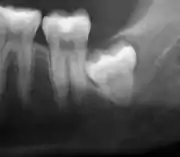

The diagnosis of impaction can be made clinically if enough of the wisdom tooth is visible to determine its angulation, depth, and if the patient is old enough that further eruption or uprighting is unlikely. Wisdom teeth continue to move to the age of 25 years old due to eruption, and then continue some later movement owing to periodontal disease.[18]

If the tooth cannot be assessed with clinical exam alone, the diagnosis is made using either a panoramic radiograph or cone-beam CT. Where unerupted wisdom teeth still have eruption potential several predictors are used to determine the chance of the teeth becoming impacted. The ratio of space between the tooth crown length and the amount of space available, the angle of the teeth compared to the other teeth are the two most commonly used predictors, with the space ratio being the most accurate. Despite the capacity for movement into early adulthood, the likelihood that the tooth will become impacted can be predicted when the ratio of space available to the length of the crown of the tooth is under 1.[5]:141